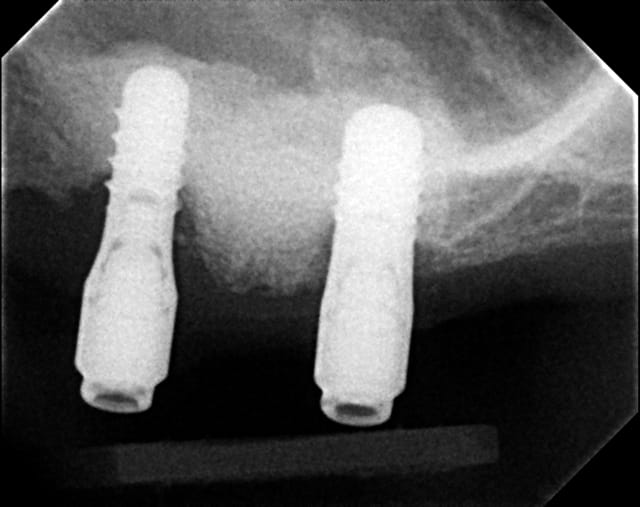

19/02/2012 à 22h20

Vous est-il arrivé de voir une résoption en apex d'un implant situé dans une greffe sinusale?

radiographie à suivre avec perte osseuse, merci

Implant juillet 2010 cnmkmg - Eugenol

Couronne  lors de la mise en bouche stvmce - Eugenol

flicflac

11/03/2012 à 19h24

la radio viendra...

perte osseuse au site de greffe sinusal en apex des implants, çà vous est déjà arrivé?

06/04/2012 à 05h22

la voila

Post greffe sinusale pdsngu - Eugenol

Il me semble que ton implant est trop enfoui, la connection se trouve au niveau osseux, donc perte ossseuse automatique avec une connection hex de ce genre.

C'est bizarre, comme si l'os non stimulé s'était résorbé. (ce qui est la règle au final ^^)

Ceramik, je parle de perte osseuse à l'apex. Le laser lock a été enfouie de moitié, ce qui est recommandé, regarde plus haut la BW à la mise en bouche. Pas de perte à ce niveau, si tu le penses trop enfouie, c'est que de l'os s'est formé en quantité non négligable, ety non c'est l'axe de la PA. PA=pas bon pour jugé du niveau osseux au collet.

Dans les cas de sinus lift non unitaire, j'utilise au plafond (greffon juxta membrane) de l'hydroxyapatite non résorbable et le reste de l'allogreffe.